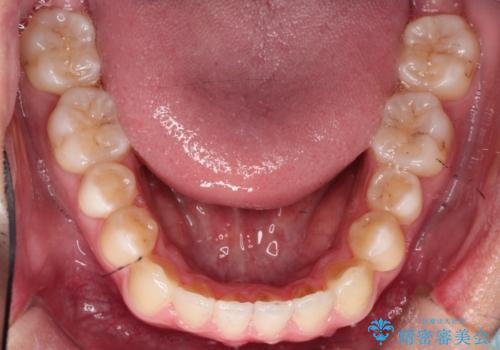

【MSE+インビザライン】前歯のガタガタ

- 前歯の凸凹を主訴に来院されました。

上の歯のアーチが狭窄していたため、骨の幅を広くするためにMSE(急速拡大装置)を使用してからインビザライン にて治療を行いました。

MSE(急速拡大装置)を用いたことで、短期間で奥歯の噛み合わせもしっかりと治すことができました。